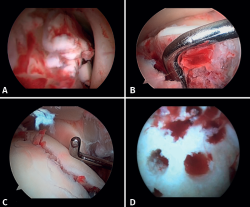

Lee describe una técnica novedosa que utiliza una guía de broca con la artroscopia de tobillo para la reducción de fragmentos articulares en fracturas del maléolo posterior. En particular, esta técnica es beneficiosa para pacientes con fracturas trimaleolares que presentan un fragmento articular deprimido, ya que permite una reducción anatómica y minimiza la necesidad de incisiones extensas(11). - Extracción de cuerpos libres. La presencia de cuerpos libres dentro de la articulación es un hallazgo común en las fracturas de tobillo. El 33% de los pacientes con artroscopia presentaron cuerpos sueltos intraarticulares retirados durante la intervención (24 de 71 casos)(12). La artroscopia permite la eliminación precisa de los cuerpos libres intraarticulares, los cuales pueden producir dolor, bloqueo o limitación de la movilidad y daño del cartílago articular(13).

- Manejo de las lesiones condrales: la bibliografía reporta tasas entre el 34 y el 91% de estas lesiones en las fracturas de tobillo. Estas lesiones se localizan frecuentemente en el astrágalo y son más comunes en fracturas graves, como las fracturas Weber C y PER. Los pacientes con lesiones del cartílago tuvieron una probabilidad 3,5 veces mayor de desarrollar osteoartritis radiográfica (puntuación de artritis de Kannus < 90) y un riesgo 5 veces mayor de presentar un pronóstico clínico a largo plazo desfavorable (puntuación de la American Orthopaedic Foot and Ankle Society –AOFAS– < 90)(14).

Si es posible, realizaremos la reinserción de fragmentos osteocondrales inestables (Figura 3). En las lesiones condrales donde no es posible reinsertar el fragmento, pueden emplearse técnicas de estimulación de reparación del cartílago(5,13).

Figura 3. A: cuerpos libres; B: lesión osteocondral; C: reducción de la lesión osteocondral; D: estimulación medular.